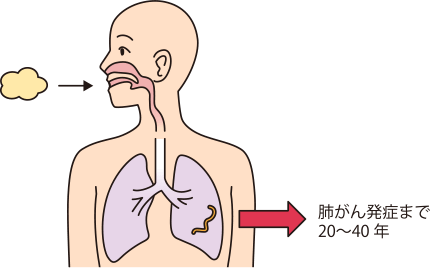

アスベスト繊維は髪の毛の5,000分の1と非常に細く、飛散すると長い時間、空気中を浮遊します。口や鼻から吸い込んでも多くはすぐに体の外に排出されますが、完全には排出されないため、わずかに残ったアスベストが肺に沈着します。アスベストは、いったん沈着すると肺の中で分解されず、長年にわたり異物としてとどまりつづけるため病気を引き起こすことがあります1,3)。

肺がんには腺がん、扁平上皮がん、大細胞がん、小細胞がんの4種類の病理組織型がありますが、アスベストはすべての組織型の肺がんを引き起こす可能性があります1)。また、肺がんの発生部位にもアスベスト特有の特徴はないとされています10)。アスベストのばく露注)から肺がんが発見されるまでの期間は20~40年と報告されています1)。